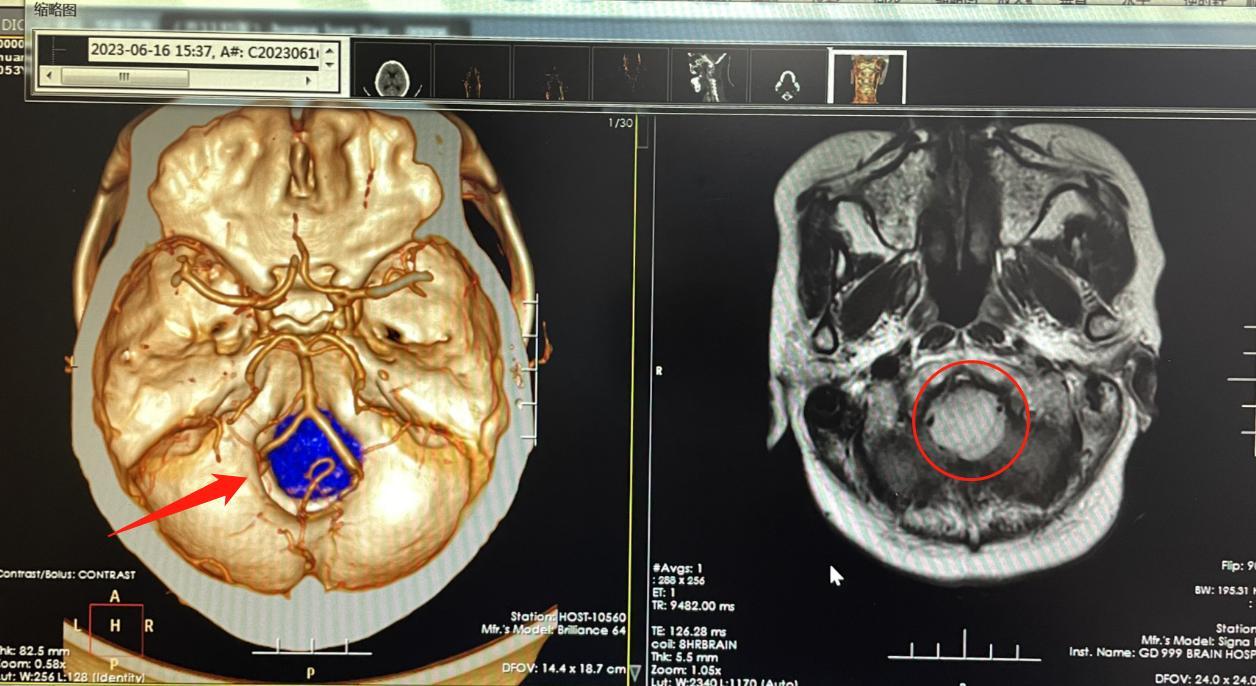

该院神经外九科主任穆林森接诊后,发现蔡阿姨的肿瘤位于斜坡-枕骨大孔区。肿瘤直径约3cm,对功能区已造成挤压,再不及时手术,可能导致瘫痪甚至危及生命。

肿瘤长在枕骨大孔区,这里空间狭小,但位置关键,肿瘤已经直接对“生命中枢”的延髓造成压迫,与血管及后组颅神经紧密粘连,手术操作稍有不慎,都可能影响患者的呼吸、心跳、吞咽等。术中,穆林森团队仔细分离肿瘤,保护神经、血管以及脑干,分块将大小约3cm×2.4cm×2.8cm的肿瘤全部切除。术后病理诊断为良性脑膜瘤。